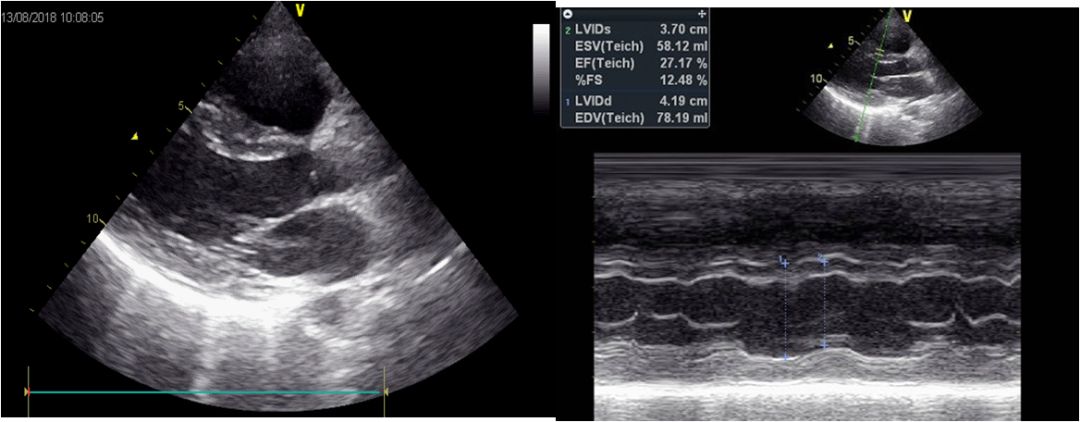

心脏彩超

➤ 左心室舒张末内径42mm,EF:27%